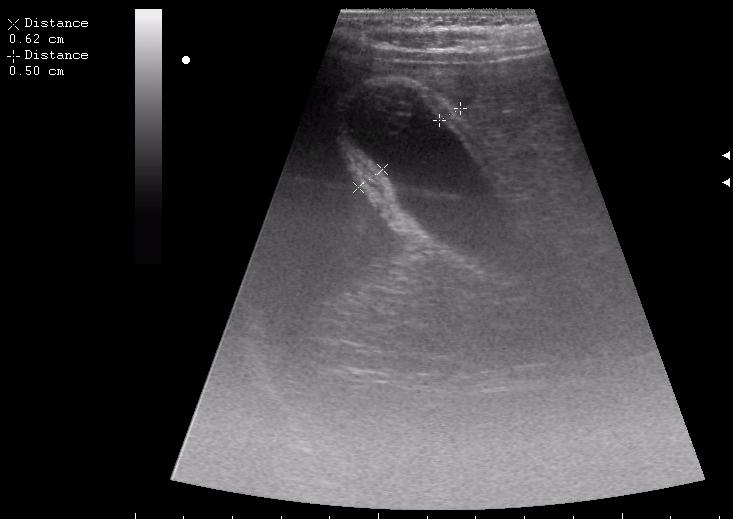

сегодня был селезёночный день.

>желтой стрелкой - это левый надпочечник?

Похоже.

Он обычно располагается больше кнутри от верхнего полюса почки и может досигать ее ворот.

Надежнее визуализировать ЛН из позиции, которую я показывал в известной Вам теме.